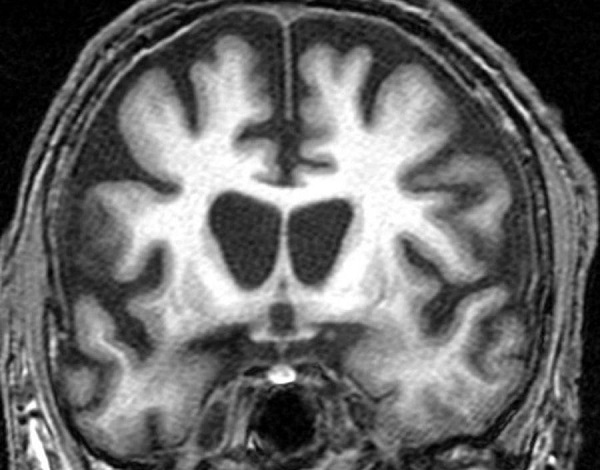

亨廷顿病(Hutington's disease)是一种具有遗传性的神经退行性疾病,患有亨廷顿病的病人每天从早到晚四肢都在不自主地颤动、甩动,就像是在跳一种奇异的“舞蹈”,故得名“舞蹈症”,甚至在睡梦中,患者都不能停止这种动作。此外,患病的人常常表情呆滞,心理和身体承受巨大的痛苦,所以患者常常在患病十年后去世。

这种病和阿尔茨海默病、帕金森病十分相似,专家认为它们都是由于蛋白质中基因突变引起的,而亨廷顿病因其产生基因突变的蛋白质名字叫做亨廷顿而得名。